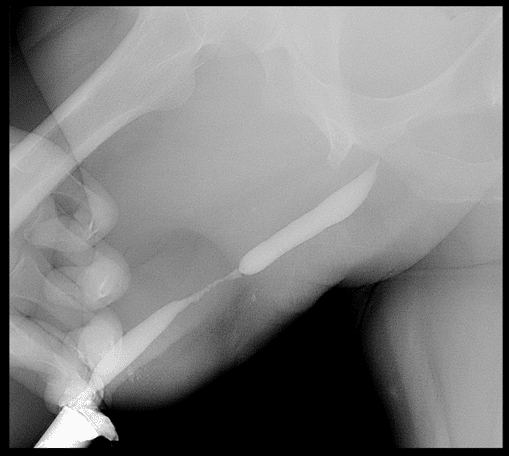

La cistouretrografía miccional (también llamada cistouretrograma, uretrocistografía o cistouretrografía retrógrada y miccional seriada) es un estudio diagnóstico fundamental que utiliza radiografías y un líquido de contraste especial para obtener una imagen clara de su uretra (el conducto por el que la orina sale de su cuerpo) y su vejiga mientras se llenan y se vacían.

El resultado es una película dinámica de cómo se comportan dichas estructuras: su forma, su calibre, si hay estrechamientos, fugas, reflujo o anomalías estructurales.

- Muestra la uretra en acción: no solo su forma estática, sino cómo se comporta durante la micción. Es un estudio «en tiempo real».

- Detecta estenosis (estrecheces) con exactitud: permite medir su longitud, ubicación y severidad —datos esenciales para planificar una cirugía.